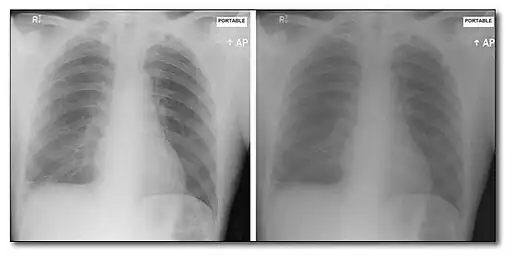

This form of image data processing is illustrated in the following figure:

A chest radiograph acquired at 56 kVp is shown in the top left panel of the figure. This is referred to as a low energy image. In the top right panel is a radiograph of the same patient's chest acquired at a high energy – 120 kVp, with 1 mm copper filtration. Results of the dual-energy processing are shown on the bottom row. The bone-subtracted image is shown in the bottom left panel and the tissue-subtracted image in the bottom right panel. Notice that the tissue-subtracted image demonstrates that the lesion in the patient's left lung is a calcified nodule, since it doesn't appear in the bone-subtracted image.